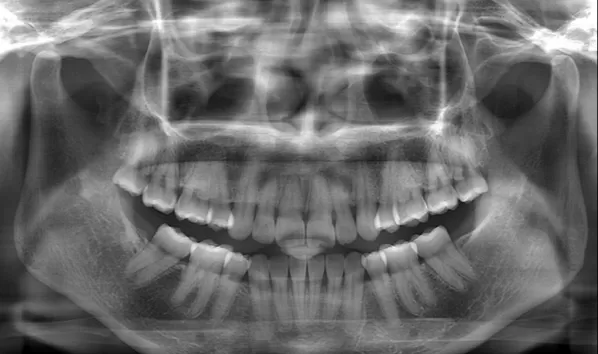

Rayons X avant le traitement

[Radiographie panoramique/Céphalogramme latéral]